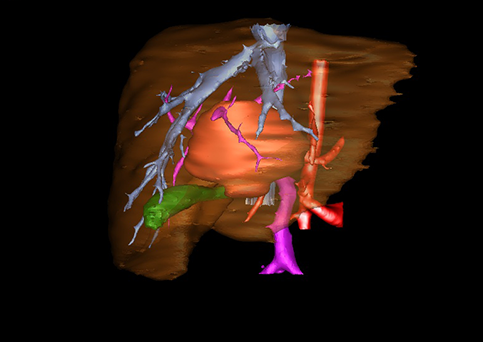

近年来由于数字医学的发展,基于可视化三维重建技术的计算机辅助手术系统极大推进了小儿肝脏肿瘤的精准手术的进步。可以立体透视肝脏解剖、精确掌握肝段的边界、精确测算肝段乃至任意血管所支配的功能体积、准确定位病灶及其与邻近血管的解剖关系,最终对不同手术方案进行比较、筛选和优化。因此,计算机辅助手术规划系统是实现精准肝切除的有力辅助工具,是未来数字外科、精准外科等21世纪外科新理念的重要技术支撑。

计算机辅助手术规划系统具有良好的操作可行性、计算准确性和三维显示效果,可半透明、交互式显示真实的肝内立体解剖关系和空间管道变异,准确计算肝内管道的直径、走行角度,两点间的垂直距离,和任意血管的支配或引流范围等传统二维影像无法获取的信息,有助于实施个体化手术,提高了手术的确定性、预见性和可控性。计算机辅助手术规划系统可直观显示预留肝脏的结构和功能,并可通过虚拟切割功能辅助术者对手术方案进行蹄选和优化,系统评估手术风险和制定对策,改变了部分二维规划的术式和切除范围,使部分二维规划认为不能切除的患者成功手术,提高了手术的根治性、安全性和病变的可切除性,更加符合精准肝脏外科的术前规划要求。详见第11章。

随着计算机技术及影像检查技术的不断发展,以精确的术前影像学和功能评估、精细的手术操作为核心的精准肝切除技术日益受到重视。基于数字医学的计算机辅助手术技术(computer-assisted surgery,CAS)则是实现肝脏精准手术操作的基础。计算机辅助手术系统(CAS)可将术前二维(two dimensional,2D)的CT/MRI影像数据进行三维(three dimensional,3D)重建,建立个体化的肝脏三维解剖模型,清晰显示肝脏内脉管系统的走行及解剖关系,还原病灶与其周围脉管结构的立体解剖构象,准确地对病变进行定位、定性和评估,制定合理、定量的手术方案,实施个体化的肝脏血管取舍分配方案及实施精准肝脏手术。一般认为CAS包括:创建虚拟的患者的图像;患者图像的分析与深度处理;诊断、手术前规划、手术步骤的模拟;术中实时导航。应用本技术后,由于可以更清晰地看出肿瘤的界限,特别是根据肝血管的显影,判断出肿瘤与门静脉及肝静脉的关系以在手术前较准确地估计出手术成功切除的可行性。以往部分根据普通强化CT判断无法手术的病例而被评估为可以成功切除并手术成功。